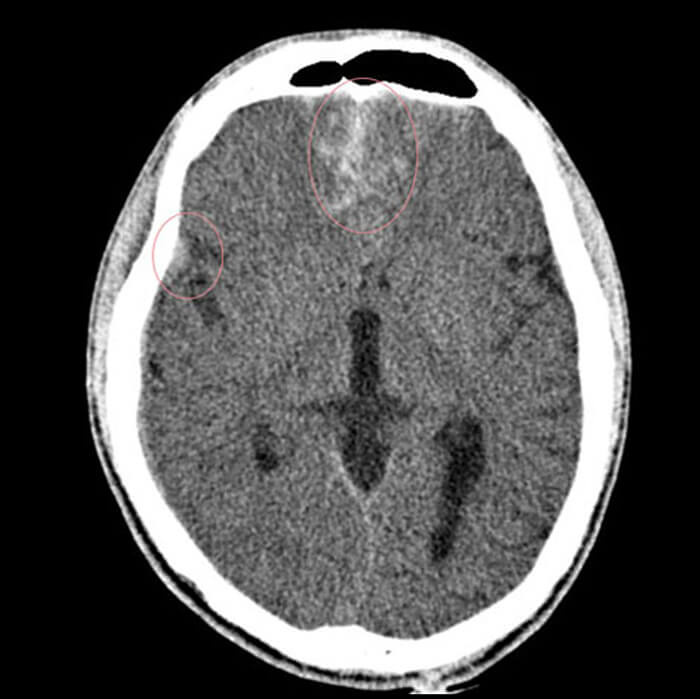

Acute Ischemic Stroke

One of the clinical cases is the Ischemic stroke, characterized by the sudden loss of blood circulation to an area of the brain, resulting in a corresponding loss of neurologic function. Acute ischemic stroke is caused by thrombotic, or embolic occlusion of a cerebral artery leading to mortality and morbidity.

The readily accessible and rapid technique that can help detect any acute ischemic stroke is the Perfusion CT Exa which will evaluate the parenchyma and determine the volume of infarct core and penumbra.

In addition, the Brain Perfusion CT exam will help to reveal 3 things:

- Suggest the potential for infarct growth

- Highlight areas of the brain with low CBV, which will be in high risk for a hemorrhagic transformation following endovascular treatment

- Capacity to select stroke patients likely to benefit from thrombolysis, based on an imaging with no contrast or intracranial hemorrhage